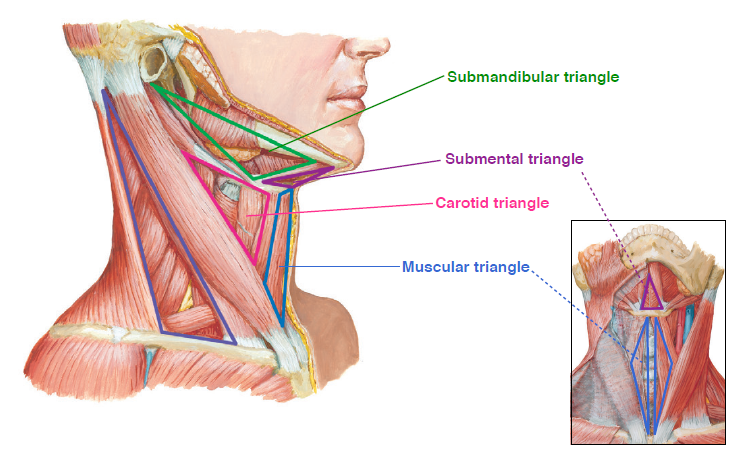

Neck

Triangle